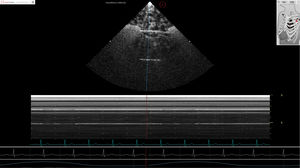

... Los módulos de patología de HeartWorks para la TTE y la TEE han sido creados para facilitar la evaluación ecocardiográfica de pacientes con alteraciones estructurales y hemodinámicas. Este módulo incluye ...

Inventive Medical Limited